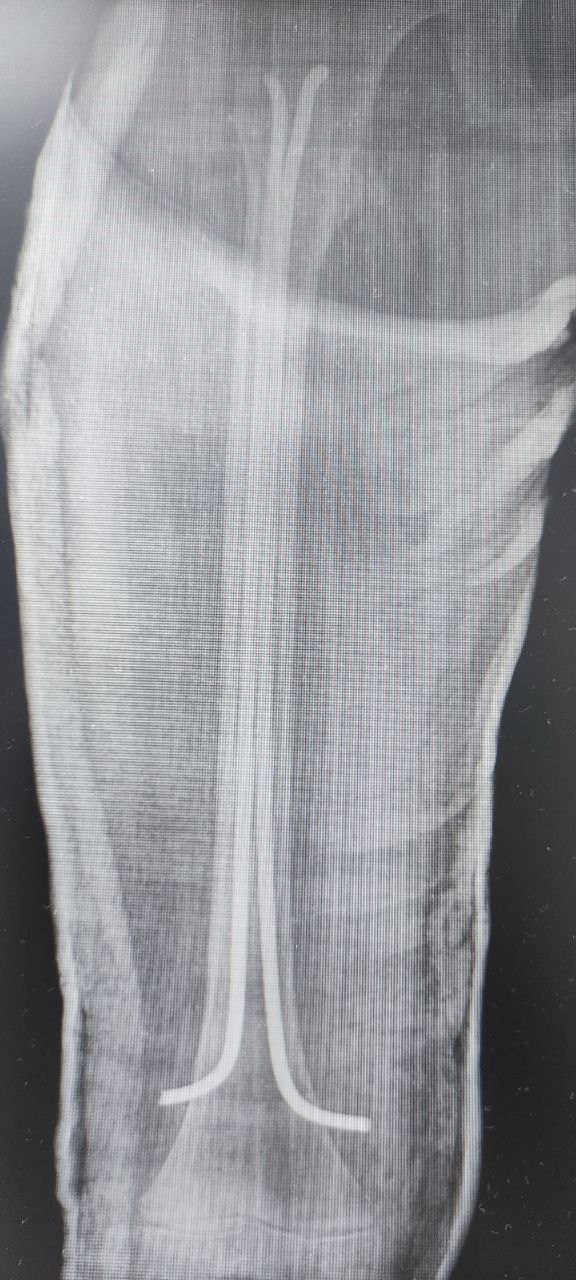

В ДРКБ накануне доставили ребенка с закрытым переломом бедренной кости со смещением. Его экстренно прооперировали, сейчас состояние стабильное.

Врачи отмечают, что травма произошла на необорудованном склоне, где отсутствовали защитные ограждения. На сращение перелома в среднем требуется 5–6 недель, а на реабилитацию – до нескольких месяцев в зависимости от индивидуальных особенностей организма и соблюдения рекомендаций.